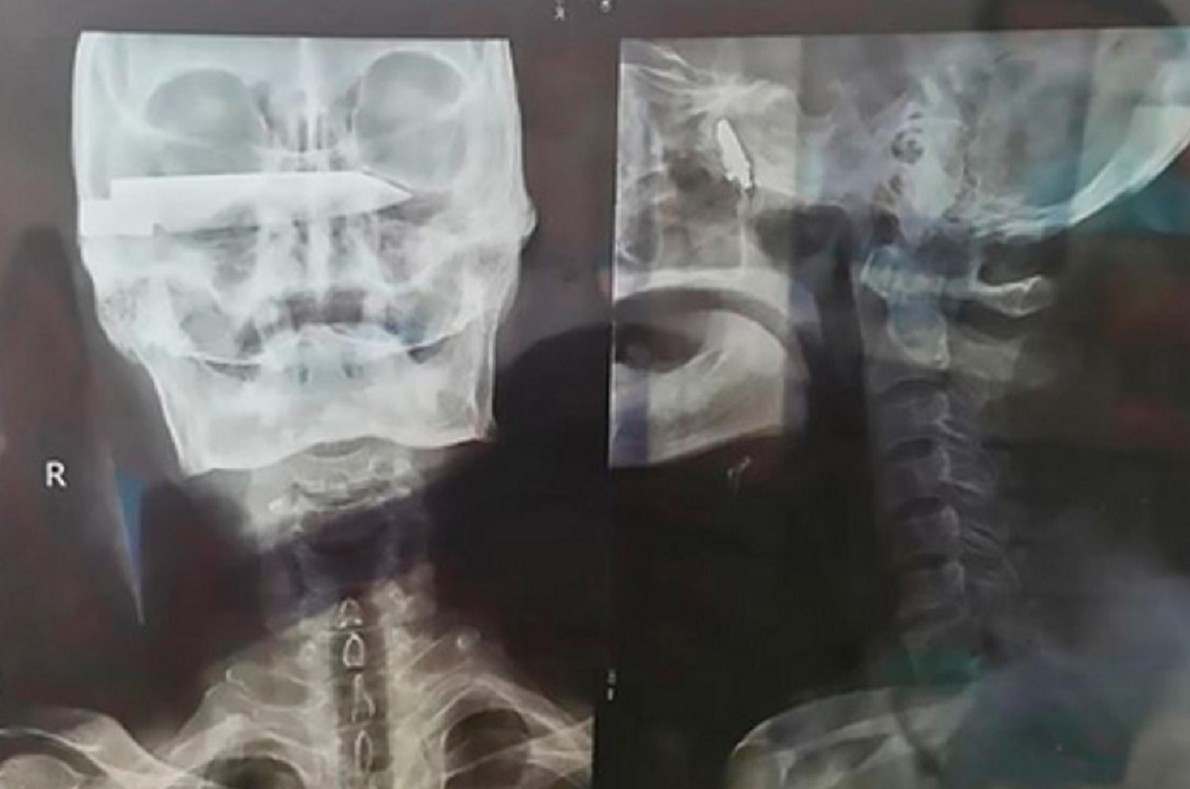

76-летний китайский фермер 26 лет проходил с лезвием ножа в голове. Лезвие было длиной в 10 см, но каким-то невероятным образом не задело никаких важных частей мозга и кровеносные сосуды.![Мужчина прожил 26 лет с лезвием ножа в голове - «Клуб - Юмора»]()

Лишь в 2012 году, когда голова стала болеть особенно сильно, фермер все-таки пошел в больницу и врачи, сделав ему рентген, изумились, увидев крепко засевшее в черепе лезвие ножа. Однако они не стали делать ему операцию, так как посчитали, что скорее всего последствия операции станут для старика хуже, чем жизнь с лезвием в голове.

Во время обследования выяснилось, что лезвие ножа передавливает глазной нерв, поэтому правый глаз и перестал видеть. При этом удалить его из черепа действительно было очень сложно, но это не остановило главного нейрохирурга клиники доктора Лю Гуанцюня.